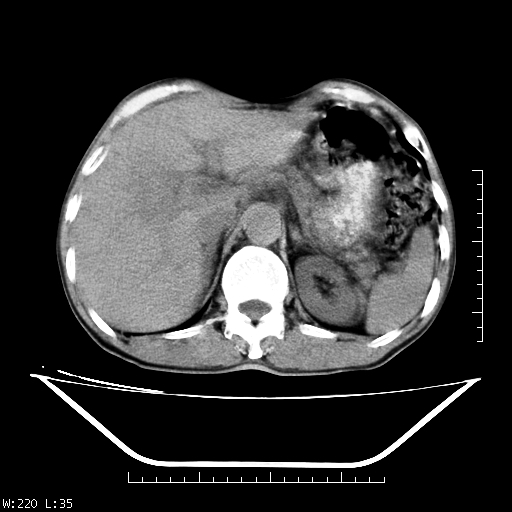

男,70,右上腹痛两月,有乙肝病史,b超提示肝占位,ct如下,请会诊。

补充:该患者afp9.24

肝右叶类圆型密度减低影,密度不均,边界清晰其内可见更低密度影,腹膜后可见小淋巴结肿大,增强扫描动脉期病灶明显强化,静脉期及延时扫描见强化不明显,快进快出表现。

1.肝右叶低密度影考虑为肝癌;

2.肝转移待除外。

平扫呈低密度占位,动脉期斑片状明显强化,病灶边缘清晰,见假包膜;门脉期呈低密度,符合肝癌快进快出强化特征

补充:该患者afp 9.24,似乎与原发性肝癌不符合,另胰头区结构正常吗?请大家继续发表高见。

平扫呈低密度占位,动脉期斑片状明显强化,病灶边缘清晰,见假包膜;门脉期呈低密度,符合肝癌快进快出强化特征,可能为纤维板型。建议介入治疗,效果会很好的。

快进快出   典型的原发性肝癌    肝门部见肿大淋巴结

肝癌,腹膜后淋巴转移不除外。